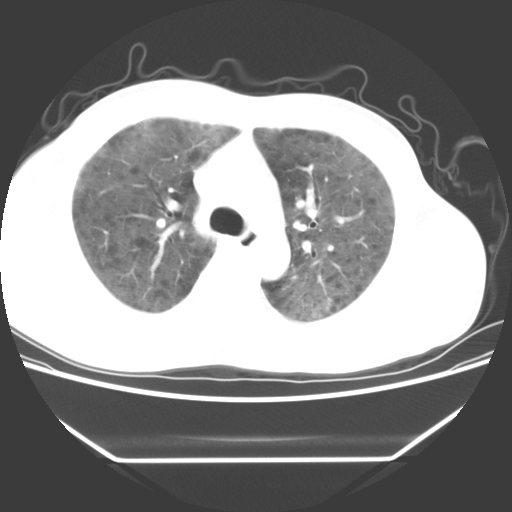

病人55岁,咳嗽,胸闷

忘了传病史了,病人55岁,咳嗽,胸闷

两肺部呈“毛玻璃”状改变,原因待查考虑感染性病变

病人是否发烧,两肺“磨玻璃”影,其间见空气支气管征和碎路石征。考虑肺泡蛋白沉着症。

两肺广泛对称磨玻璃样影,密度不均,考虑机遇性肺部感染。

双肺弥漫磨玻璃样病变,病史很重要。有感冒或发烧史,甲流不除外。无发烧可考虑肺泡蛋白沉积,但肺泡蛋白沉积边缘往往较清晰,与正常肺组织分界清晰

两肺弥漫间质性病变,考虑肺泡蛋白沉着症。建议进一步检查。

两肺“磨玻璃”影,其间见空气支气管征和碎路石征。考虑肺泡蛋白沉着症。